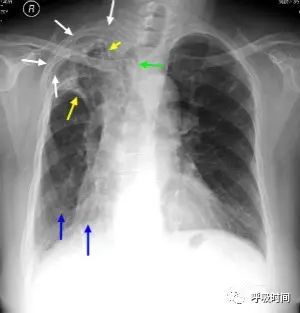

图片

图 9 肺纤维化病变影——陈旧性肺结核。右肺上叶可见条索状影及斑片状影(黄箭头);右肺门上移,下肺纹理呈垂柳状(蓝箭头,提示上叶体积缩小);气管右移、弯曲(绿箭头,提示上叶体积缩小);右侧胸廓顶部胸膜增厚(白箭头,即肺尖帽征)